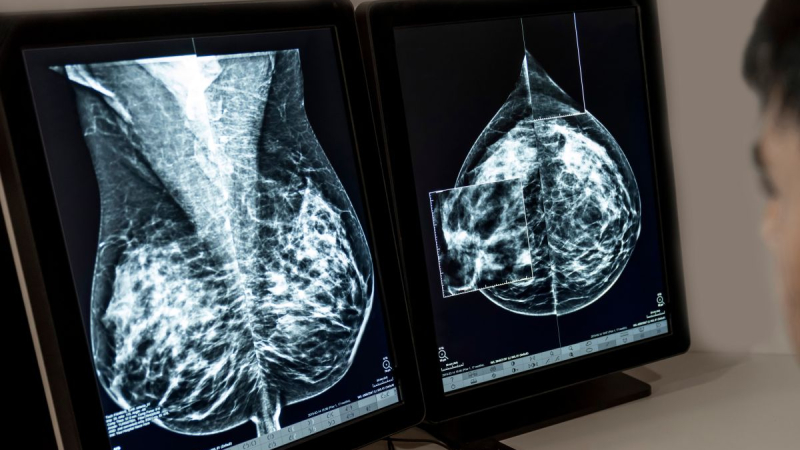

El cáncer de mama es el cáncer que se diagnostica con mayor frecuencia en Europa, y aproximadamente el 70% de los casos, en etapas tempranas de la enfermedad. A pesar de las opciones terapéuticas actuales, las personas diagnosticadas con cáncer de mama localizado HR+/HER2- en estadios II y III siguen corriendo el riesgo de que su cáncer reaparezca a largo plazo, a menudo como una enfermedad avanzada incurable.

La aprobación de ribociclib se basa en los datos del estudio de Fase III NATALEE, que incluyó una amplia población de pacientes con cáncer de mama localizado HR+/HER2- en estadios II y III, incluyendo aquellos sin afectación ganglionar con elevado riesgo de recaída. El estudio mostró una reducción significativa y clínicamente relevante del 25,1% en el riesgo de recaída de la enfermedad con este fármaco adyuvante en combinación con terapia endocrina (TE), en comparación con TE en monoterapia. El beneficio de supervivencia libre de enfermedad invasiva (SLEi) se observó de forma consistente en todos los subgrupos de pacientes.